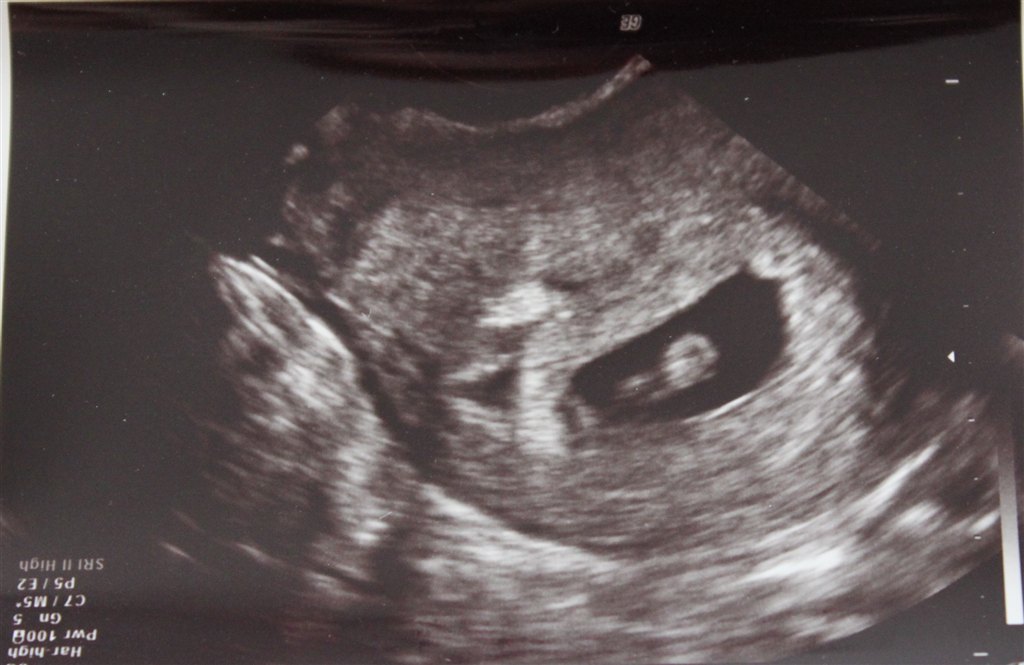

Jeg var til scanning, da jeg var 7+1 (se de vedhæftede billeder).

Den ene af mine havde gemt sig lidt, så den er lidt utydelig

Vedhæftede fotos (klik for at se i fuld størrelse)